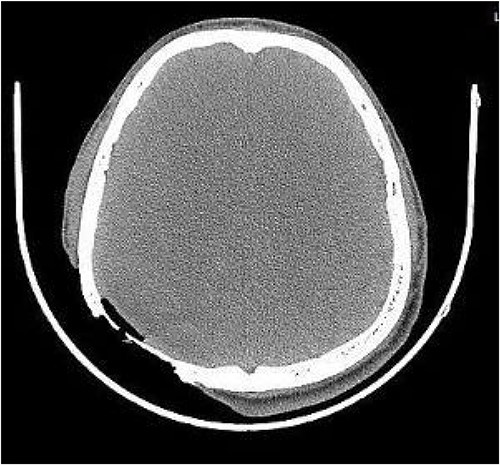

On post-debridement Day 16, the exposed skull was ~8 cm × 9 cm, the bone was dark, and the cortex of the skull defect was ~3 cm × 3 cm (Fig. 1). Computed tomography showed the presence of gas inside the skull (Fig. 2). Bacterial culture of wound secretions reported Proteus mirabilis. During residual wound debridement, a defect of ~1 cm × 1 cm of the inner plate of the skull and dura mater exposure were found (Fig. 3). Subsequently, two skin dilators were embedded under normal scalp and were dilated by regularly injecting saline (Fig. 4). The exposed dura was regularly rinsed with saline to reduce bacterial colonization.

Defect of the inner plate of the skull of ~1 cm × 1 cm, with exposure of the dura mater.